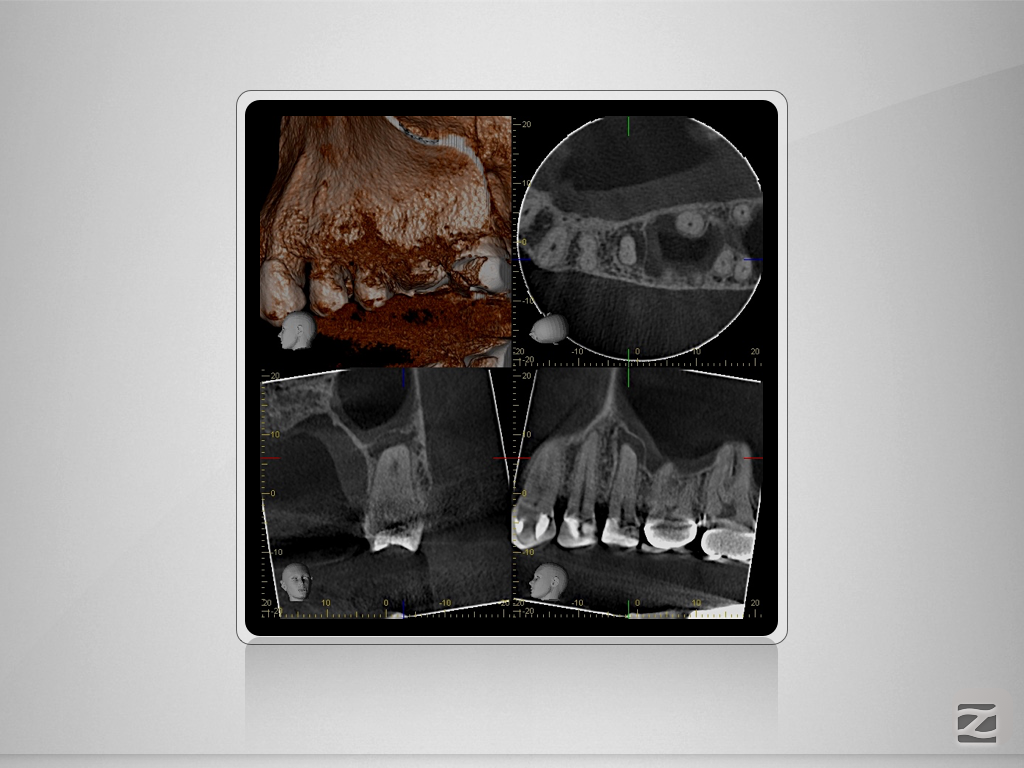

25D.006

Tiefe Gabelung